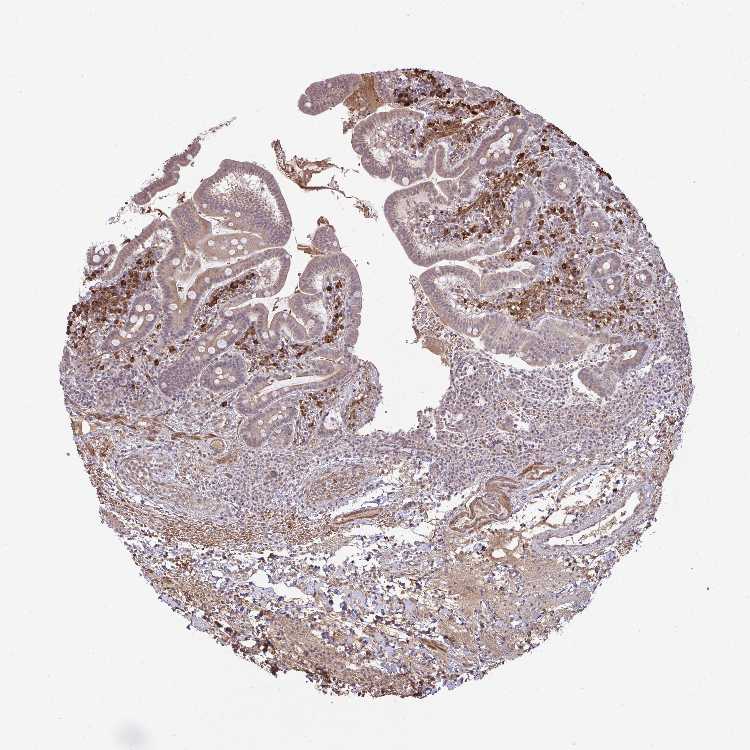

SMALL INTESTINE - Antibody stainingi

Antibody staining in the annotated cell types in the current human tissue is reported as not detected, low, medium, or high, based on conventional immunohistochemistry profiling in selected tissues. This score is based on the combination of the staining intensity and fraction of stained cells.

Each image is clickable and will lead to virtual microscopy that enables deeper exploration of all samples and also displays staining intensity scores, fraction scores and subcellular localization as well as patient and tissue information for each sample.

Antibody HPA054512Antibody HPA059951

Glandular cells MediumHigh